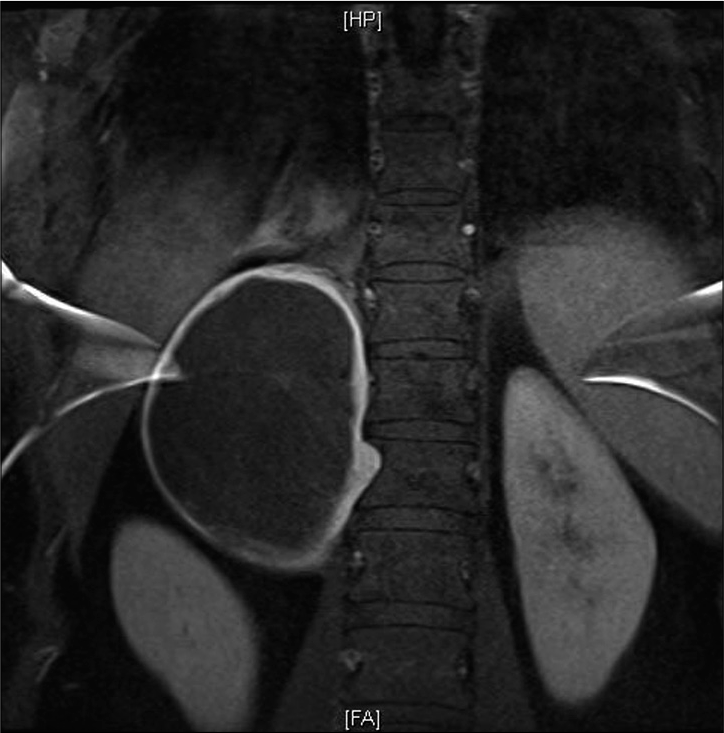

Unraveling a rare cause of spinal stenosis: Coexistent AL and ATTR amyloidosis involving the ligamentum flavum